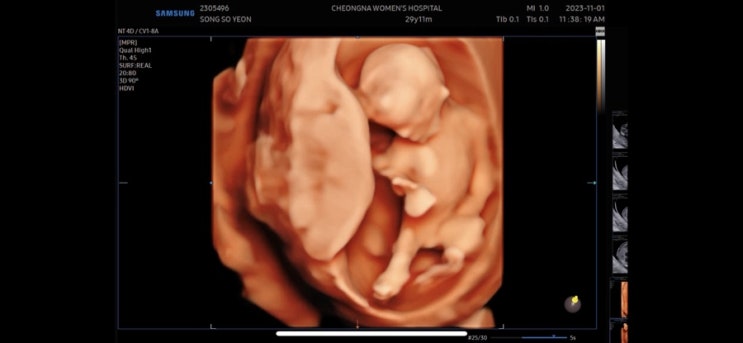

다솜이 첫만남

9/16일 첫만남 한번의 유산 다시 만난 소중한 아가 아프지말고 건강하게만 태어나다오 “애틋하게 사랑하는...

다솜이

11/1